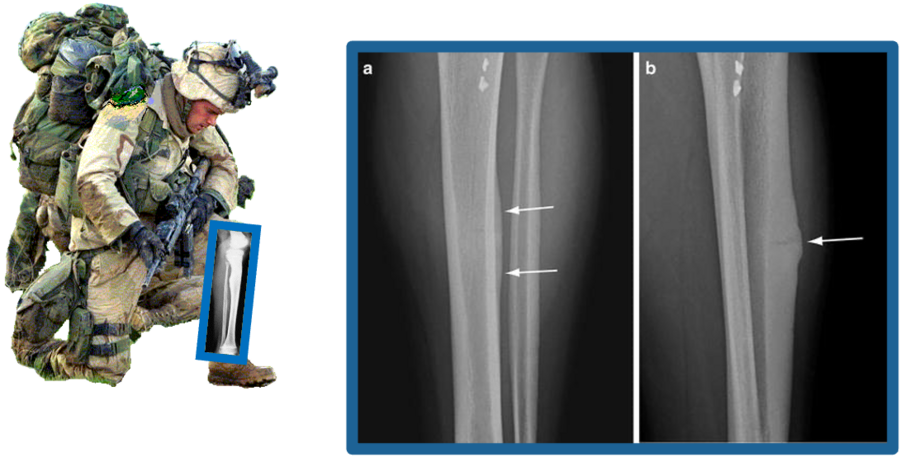

Working in partnership with USARIEM through the ARMI study, we investigate why some recruits are more vulnerable to stress​ fractures during basic training. Our research combines state-of-the-art imaging, physical performance testing, and biomarker analysis to pinpoint risk factors and guide prevention strategies. The ultimate goal is to keep service members healthy, resilient, and mission-ready while informing approaches to stress fracture prevention in athletes and other physically active populations.